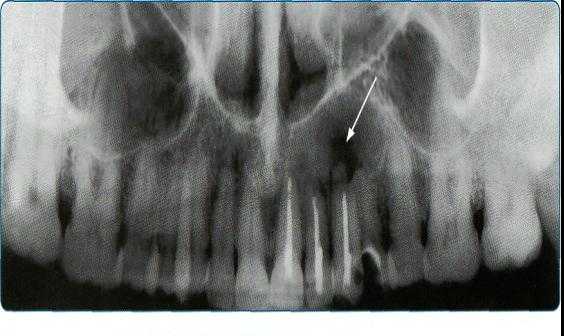

Ортопантомограммы демонстрируют взаимоотношения зубов верхнего ряда с дном верхнечелюстных пазух и позволяют выявить в нижних отделах пазух патологические изменения одонтогенного генеза.

Основной методикой рентгеновского исследования челюстно-лицевой области является ортопантомография (ОПТГ), которая совершенствуется, переходя на цифровой способ получения изображения. На ОПТГ отображается панорамный рентгеновский снимок зубочелюстной системы пациента, на котором видны верхняя и нижняя челюсти, развёрнутые в плоскости, корни, каналы зубов, имеющиеся имплантаты, ортопедические конструкции, пломбы, а также пародонтальные щели, гайморовы пазухи, носовые

ходы, височно-нижнечелюстные суставы, нижнечелюстной канал.

Методика оправдана для предварительных скрининговых исследований широких масс населения, поэтому активно используется при диспансеризации. Ортопантомография превосходит стандартные рентгеновские снимки и позволяет дифференцировать кисты одонтогенного и риногенного происхождения, оценивать окружающие структуры лицевого отдела головы. Однако ОПТГ имеет ряд ограничений — изображение является плоскостным, что не дает возможности оценить распространение кистозного процесса и состояние окружающих структур, а также не в полной мере дает информацию о состоянии корневых каналов.